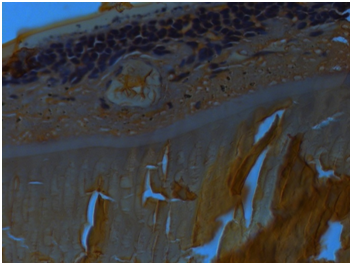

Transparent crystalline lens was separately examined and showed neovascularisation (Figure 2a-d). Enucleated eye ball showed tumour occupying almost entire vitreous cavity. Crystalline lens was seen separately which looked slight yellow and transparent. Three blood vessels were seen in the lens in the peripheral edge and were documented under background illumination. Portion of the lens was again dissected and haematoxyline & eosin (H&E) stain was carried out and it revealed regressed blood vessels in the cross section. Haematoxylin was put on the slide for 10-15 minutes followed by a wash in the running water, then one dip is made in 1% acid alcohol, slide was washed followed by addition of 0.4 % of ammonia for 1 minute. Third wash was made. Eosin was put on the slide for 1 minute and further washing is carried out. Xylene was added. Slide was dried and mounted for microscopic viewing. Study of the specimen in H&E stain showed normal cornea with focal iris neovascularisation. An endophytic tumor was seen in the vitreous cavity with numerous Flexner Wintersteiner (FW), Homer Wright (HW) and few new true rosettes4 (Figure 3). Zones of necrosis seen without any calcifications. Few vesicular cells along with basophilic undifferentiated cells and occasional apoptotic bodies were noted.5 Neovascularization of lens was also documented in H&E stained eyeball (Figure 4). Few pigment migrations were also noted. Exudations were seen in the section. Lateral calottes showed superficial involvement of the retinal pigment epithelium (RPE). The sclera was normal. Cut end of the optic nerve did not show tumor involvement. Immuno-Histochemisty (IHC) of the tumor was done for nueron specific enolase (NSE), glial fibrillary acidic protein (GFAP), p53, BCL2, transforming growth factor β (TGF-β). NSE and p53 were positive in the tumor sample and others were negative. GFAP, BCL2, TGF beta were negative in the lenticular portion of the eyeball as well as the adjoining basophilic tumour zone. Patient was reviewed by an oncologist at the regional cancer centre (Figure 5).

Figure 5 A cluster of tumor cells encroaching the RPE in H&E stain (X200).